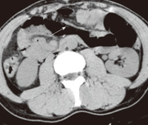

CT κοιλίας 1 (ένα) έτος μετά από χειρουργική επιδιόρθωση της οσφυϊκής κήλης. Πλήρης εξάλειψη του ελλείμματος (Ευγενική παραχώρηση Dr. V. Penopoulos)